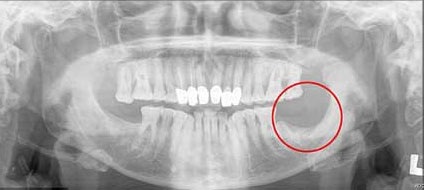

Bà Musa cho biết lý do bà phải đến gặp bác sĩ để yêu cầu nhổ chiếc răng khôn là do chiếc răng đó cọ xát với má khiến chảy máu rất nhiều.

Trước khi đi nhổ răng, bà Musa đã cẩn thận tới Bệnh viện Derbyshire Royal để kiểm tra, các bác sĩ ở đây sau khi làm lành vết thương ở má của bà cũng khuyên bà nên nhổ chiếc răng khôn để tránh làm tổn thương cho má. Các bác sĩ đã viết sơ lược về tiền sử bệnh của bà để bác sĩ nha khoa sẽ lưu ý trước khi nhổ răng.

Vài ngày sau khi nhổ răng, bà bắt đầu bị những cơn đau nhức liên tục hành hạ. Vết thương trong chỗ nhổ không thể tự lành được mặc dù bà đã phải dùng rất nhiều phương pháp giúp làm lành, thậm chí cả một phần xương hàm của bà cũng được bỏ đi để giúp bà thoát khỏi sự đau nhức do vết thương nhổ răng để lại.